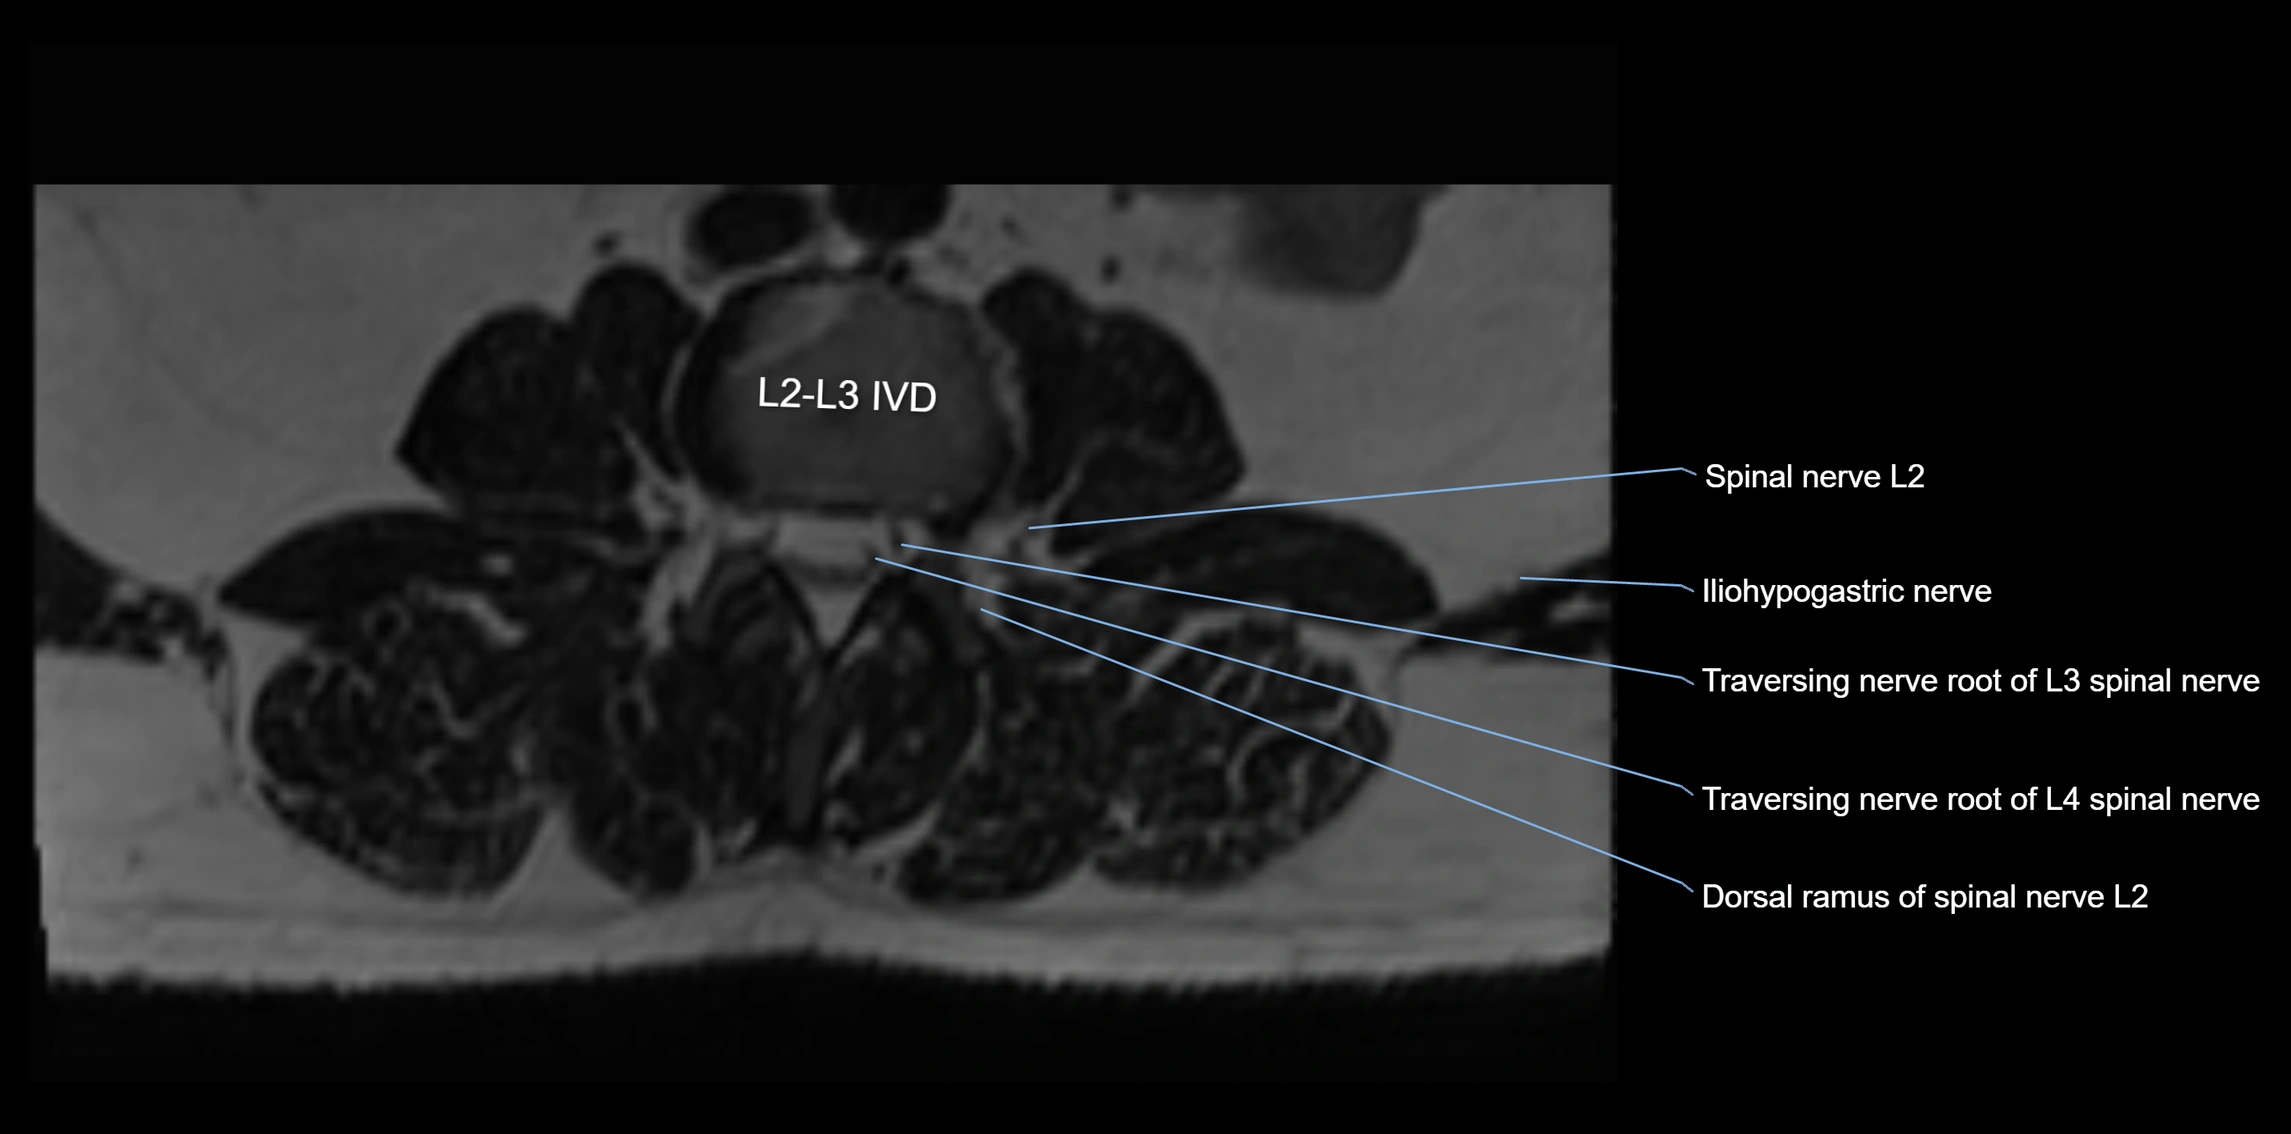

MRI Appearance

T1-weighted images:

• Nerve appears as a very thin low-to-intermediate signal intensity structure

• Surrounded by bright fat, aiding visualization

T2-weighted images:

• Nerve shows intermediate to mildly hyperintense signal compared to muscle

• Pathological involvement appears brighter

STIR (Short Tau Inversion Recovery):

• Normal nerve appears dark

• Inflamed or entrapped nerve appears bright hyperintense

T1 Fat-Sat Post-Contrast:

• Normal nerve enhances minimally

• Pathologic nerve (neuritis, entrapment, tumor infiltration) shows focal or diffuse enhancement

3D T2 SPACE / CISS:

• Nerve appears intermediate to mildly hyperintense compared to muscle

• Surrounded by bright fat or CSF, improving visualization

• Best sequence for mapping small pelvic nerves such as the anococcygeal